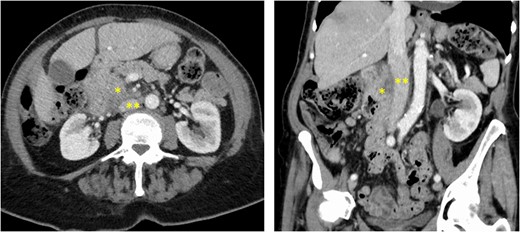

Preoperative CT-scan showing a huge duodenal mass (*) of 7 cm in size developed from the second part of the duodenum, close to the anterior wall of the infrarenal IVC (**).